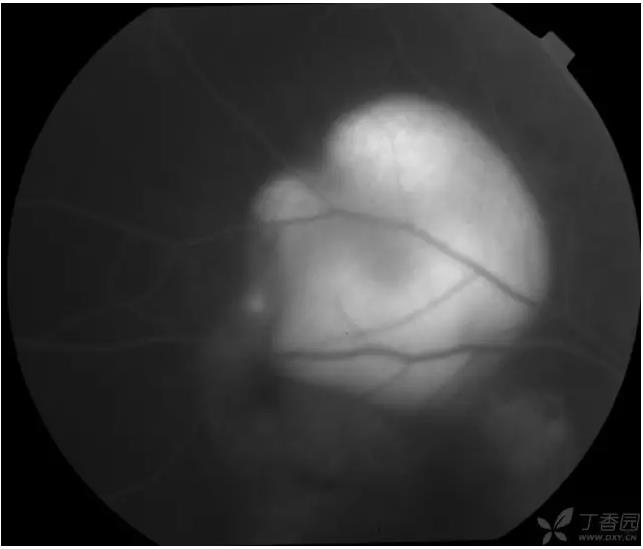

▼视乳头高度水肿